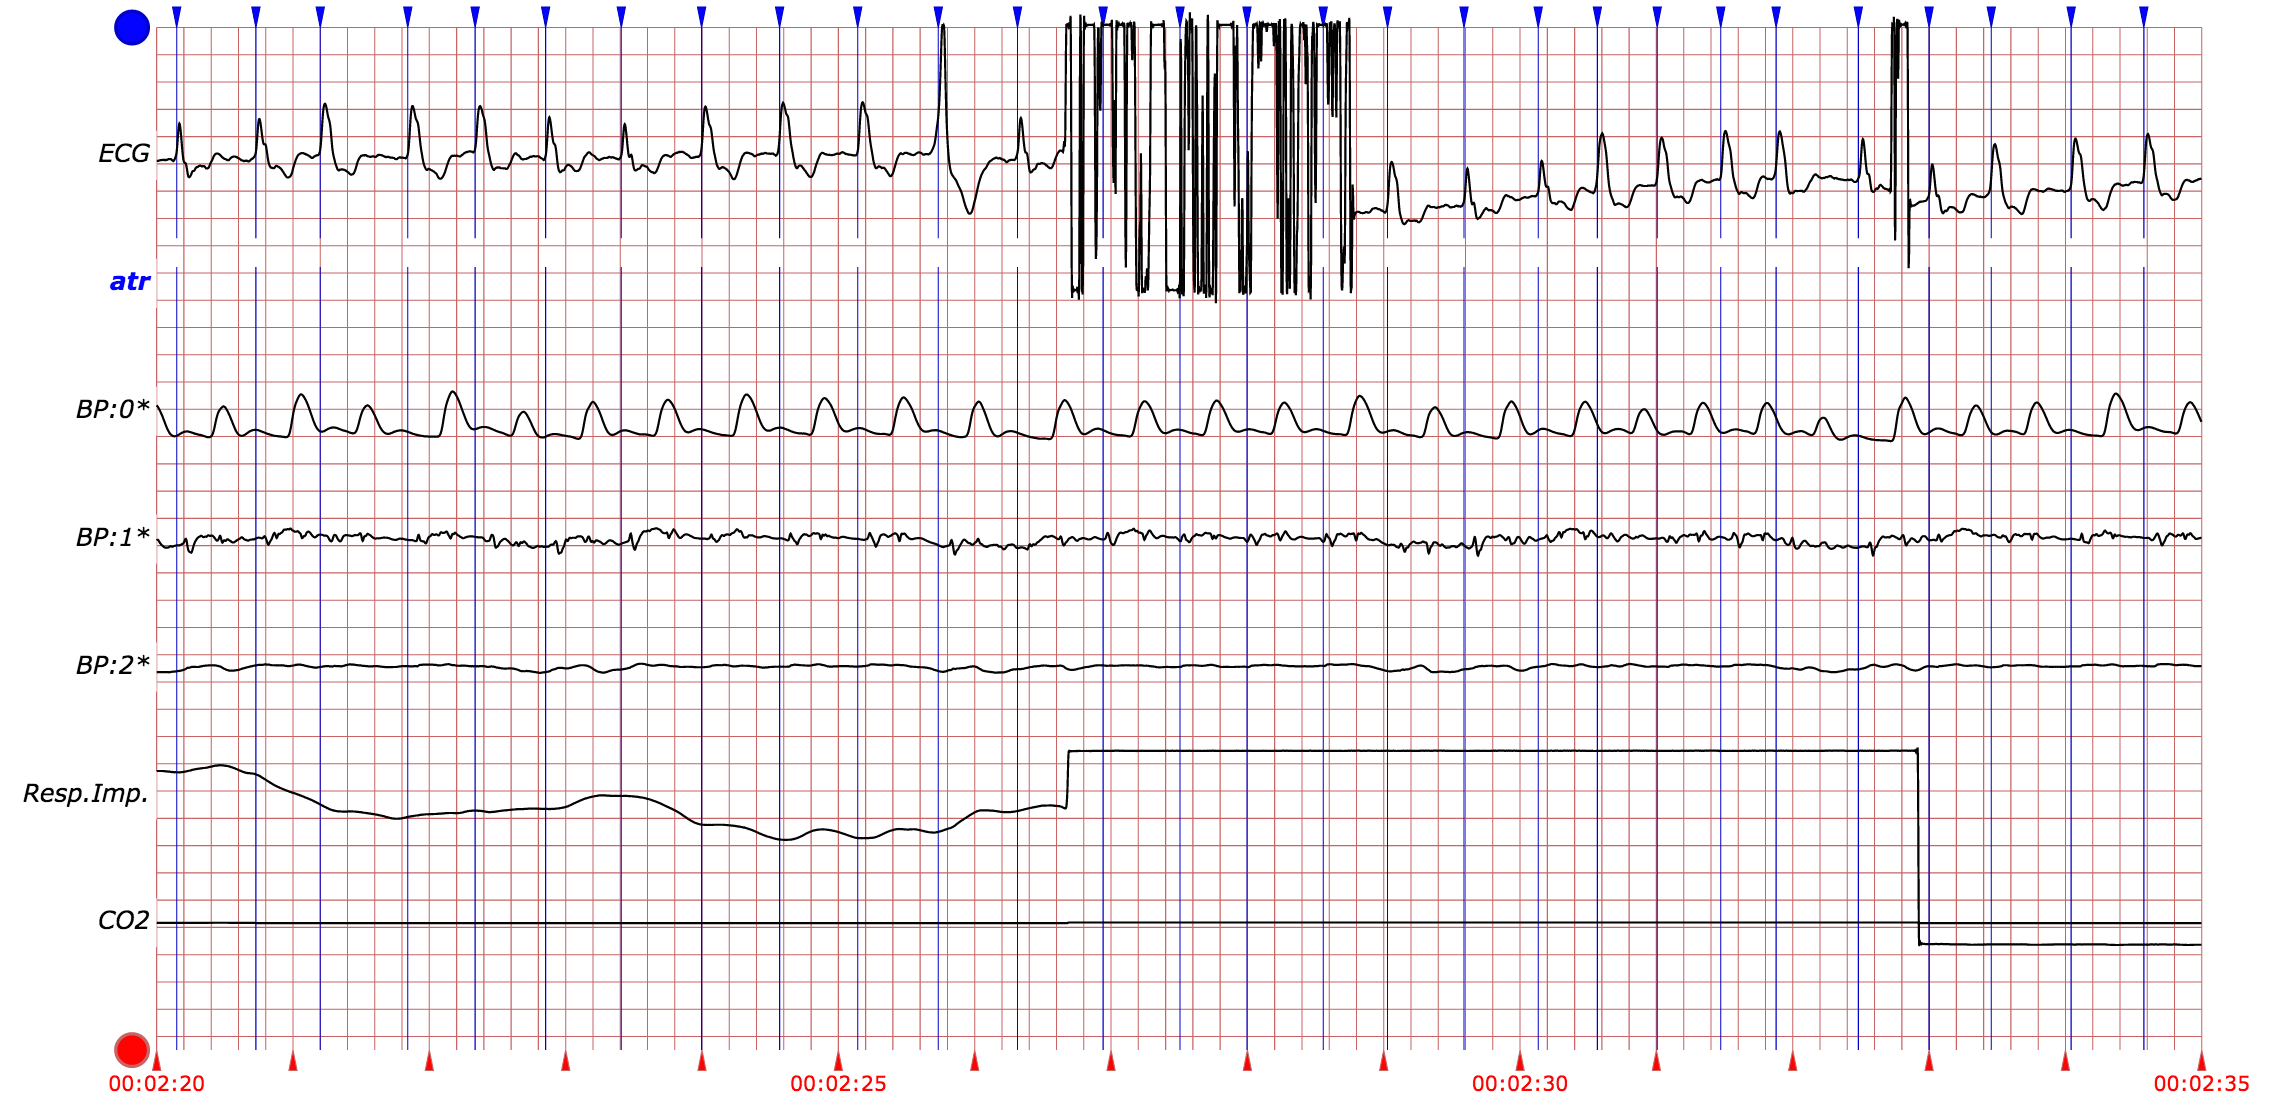

Standard methods for heart beat detection typically include signal processing algorithms that rely on a particular lead for a particular signal. This naive approach is already problematic because of the potential for dropped signals. Figure 1 provides an example of dropped signals within a single piece of data. This shows that for a given patient, across a relatively short period of time, it is possible for either the ECG or the ABP signal to simply flat-line and yield no useful information. These dropped signals occur for a variety of reasons, including but not limited to technical malfunctions or the detachment of sensors due to patient movement. In these cases, any signal processing algorithm that naively depends on a single signal’s lead will fail to provide useful data for extended periods of time.

In Figure 2, the middle of the ECG signal has a clear example of an artifact. The regular QRS complexes are disturbed, leaving a signal that bears no recognizable patterns. Artifacts can be the manifestation of a patient brushing their teeth, bumping into something, or simply rolling around in their sleep. They complicate the detection of heart beats, because the artifacts can corrupt the signals in a variety of ways, thereby rendering any naive switching algorithm insufficient. Ultimately, the goal is to robustly detect heart beats despite the occurrence of artifacts, noise, and dropped signals. In doing so, patient monitoring systems in hospitals can become much more efficient, reducing ICU false alarm rates.